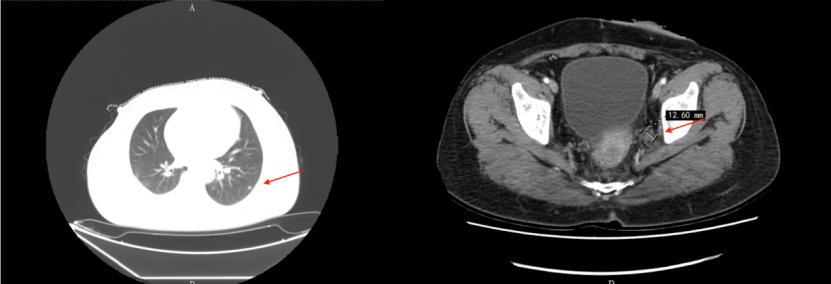

(4)患者停药4个月后常规复查发现双肺新发结节,左侧盆壁侧方有肿大淋巴结。2019.03.06 增强CT如下,同时肿瘤标志物cea升高至7.83ng/ml。考虑肿瘤复发。

给予患者二线方案FOLFIRI+贝伐珠单抗方案化疗11周期(2019.03—2019.11)。治疗期间复查CT及MRI肺部及盆腔病变稳定。

(7)2021.07 患者复查疾病再次进展,肺部出现多发新发结节,原转移灶增大。盆腔侧方淋巴结变化不大。

患者拒绝强化疗方案,根据2021年CSCO指南进展,给予曲氟尿苷替匹嘧啶(TAS-102)+贝伐珠单抗治疗,病情稳定。